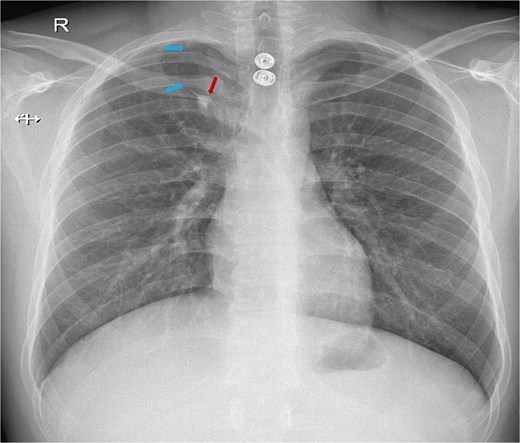

The CT scan revealed an azygos lobe in the right upper lung, definitively ruling out pneumothorax. The azygos vein was situated at the inferior edge of the curvilinear azygos fissure, which extended toward the right tracheobronchial angle (Fig. 2). With preserved lung markings within the lobe, ruling out pneumothorax, a retrospective study of the CXR verified that the lucency matched the azygos fissure.

CT chest demonstrating the azygos lobe. (A) Coronal view with blue arrows indicating the azygos fissure and the red arrow pointing to the azygos vein. (B) Axial view shows the azygos fissure is seen as a curved, sharply marginated line in the right upper lobe, typically situated anteromedially.